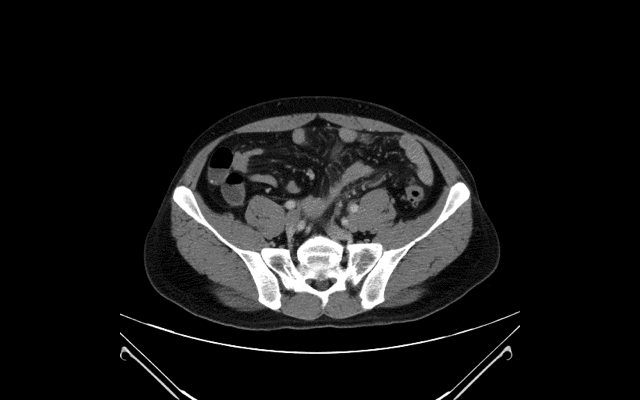

進行了ABDOMEN的掃描後,

就要進行左下腹疼痛部位的重點掃描,

可見在sigmoid colon轉往骨盆處有明顯的發炎,

腸壁變厚: wall thickening

脂肪發炎: fat stranding (echogenic fat)

圓頂突起: dome sign (台北大巨蛋 = Taipei Dome)

POCUS impression:

Sigmoid diverticulitis